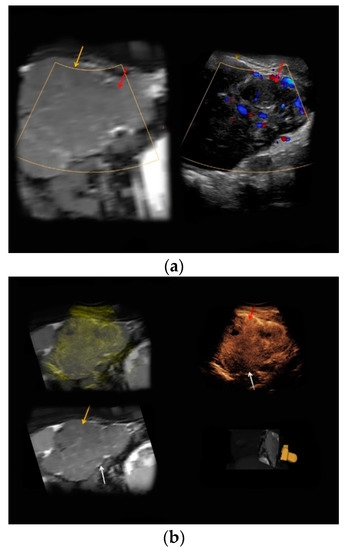

| #3 | 34 | 25 | Necrotic uterine fibroid | B-mode: inhomogeneous, hypo-/hyperechoic, 15 cm Doppler: no hypervascularization CEUS: slight contrast enhancement | inhomogeneous, predominantly T1-hypointense, T2-hypointense |